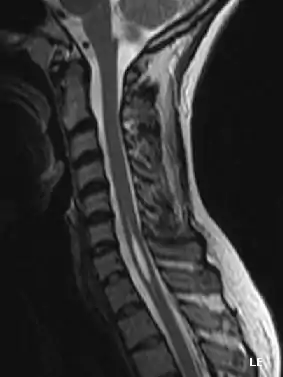

La siringomielia es un trastorno en el cual se forma un quiste dentro de la médula espinal. Este quiste se conoce como siringe o syrinx. Con el tiempo, el syrinx se expande y alarga, destruyendo el centro de la médula espinal. Puesto que la médula espinal conecta el cerebro con los nervios de las extremidades, este daño causa dolores, debilidad y rigidez en la espalda, los hombros, los brazos o las piernas. Otros síntomas pueden incluir dolores de cabeza (cefalea) y pérdida de la capacidad de sentir calor o frío extremos, especialmente en las manos. Cada paciente tiene una combinación distinta de síntomas.

Una serie de lesiones pueden obstruir el flujo normal del líquido cefalorraquídeo y redirigirlo hacia la médula espinal. Esto da lugar a la formación del syrinx o siringe, el cual se llena de líquido cefalorraquídeo. Las diferencias de presión a lo largo de la médula espinal hacen que el líquido se mueva dentro del quiste. Se cree que este movimiento continuo del líquido da lugar al crecimiento del quiste y causa daños adicionales a la médula espinal.

Un tratamiento se basa en la sección quirúrgica del filum terminale.[2] La sección de este ligamento consiste en una pequeña apertura del hueso sacro, al final de la espalda donde no existe el problema de alterar la mecánica de la columna vertebral, aunque puede provocar dolor pélvico crónico. No es una intervención exenta de riesgos y posibles complicaciones. Una vez visualizado el filum terminale este se secciona con técnicas microquirúrgicas.

La mayoría de los síntomas se deben a la lesión irreversible del tejido nervioso, y este no es capaz de reemplazarlo; sin embargo, parece ser que en la siringomielia idiopática la sección del filum terminale detiene la enfermedad.[4] El quiste resultado de la necrosis celular queda igual, pero puede desaparecer cuando espontáneamente se abre el espacio que rodea la médula espinal o lo hace hacia el centro de ella donde existe un conducto, el conducto ependimario, que comunica el centro de la médula con las cavidades cerebrales.

La sección del filum terminale provoca dos efectos beneficiosos: detiene la muerte de los tejidos debido a la tracción de la médula, y disminuye el efecto masa del quiste al relajar la médula espinal.[5]